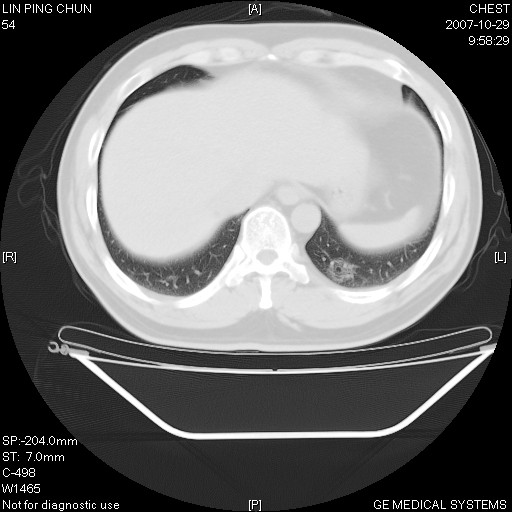

标题: CT10239:男,42Y.我自己的胸部CT扫描,今天10点突然咯血一次。

我自己胸部ct扫描,求助大家,我自己还不能给自己诊断。其他层面纵隔窗无异常。

补充:男,42y.今天10点突然咯血一次。余无异常。

左肺下叶后基底段小片结节状影,内部似见同心圆状分布条絮状影,整个病灶,质不实.局部见增粗血管影.

考虑;球形肺炎可能大.自已的身体如此重要,不进一步局部薄层及hrct?

左下肺后基底段磨玻璃样影,很多病都可以。不能吊以轻心。应该做局部增强hrct进一步检查,并严格抗炎治疗后复查或经皮活检。

左下肺后基底段小斑片泪膜玻璃样影,其内可见空泡影,边缘可见小毛刺影。建议抗炎治疗复查,肿瘤待排

老兄,我建议您把病灶做个薄层处理,靶重建,然后上传过来,您仔细看看现在的病灶特点,小病灶,边界清,内见空泡征,高度警惕细支气管肺泡癌,最好的结局就是aah(不典型性腺瘤样增生).我会密切关注您的.另外,现在您可正规抗炎治疗半月后,与3个月后复查观察病灶变化,如没有太大变化,我建议您立即手术,放心!即使是肺癌也是早期,不会影响您的生命的,祝您好运.